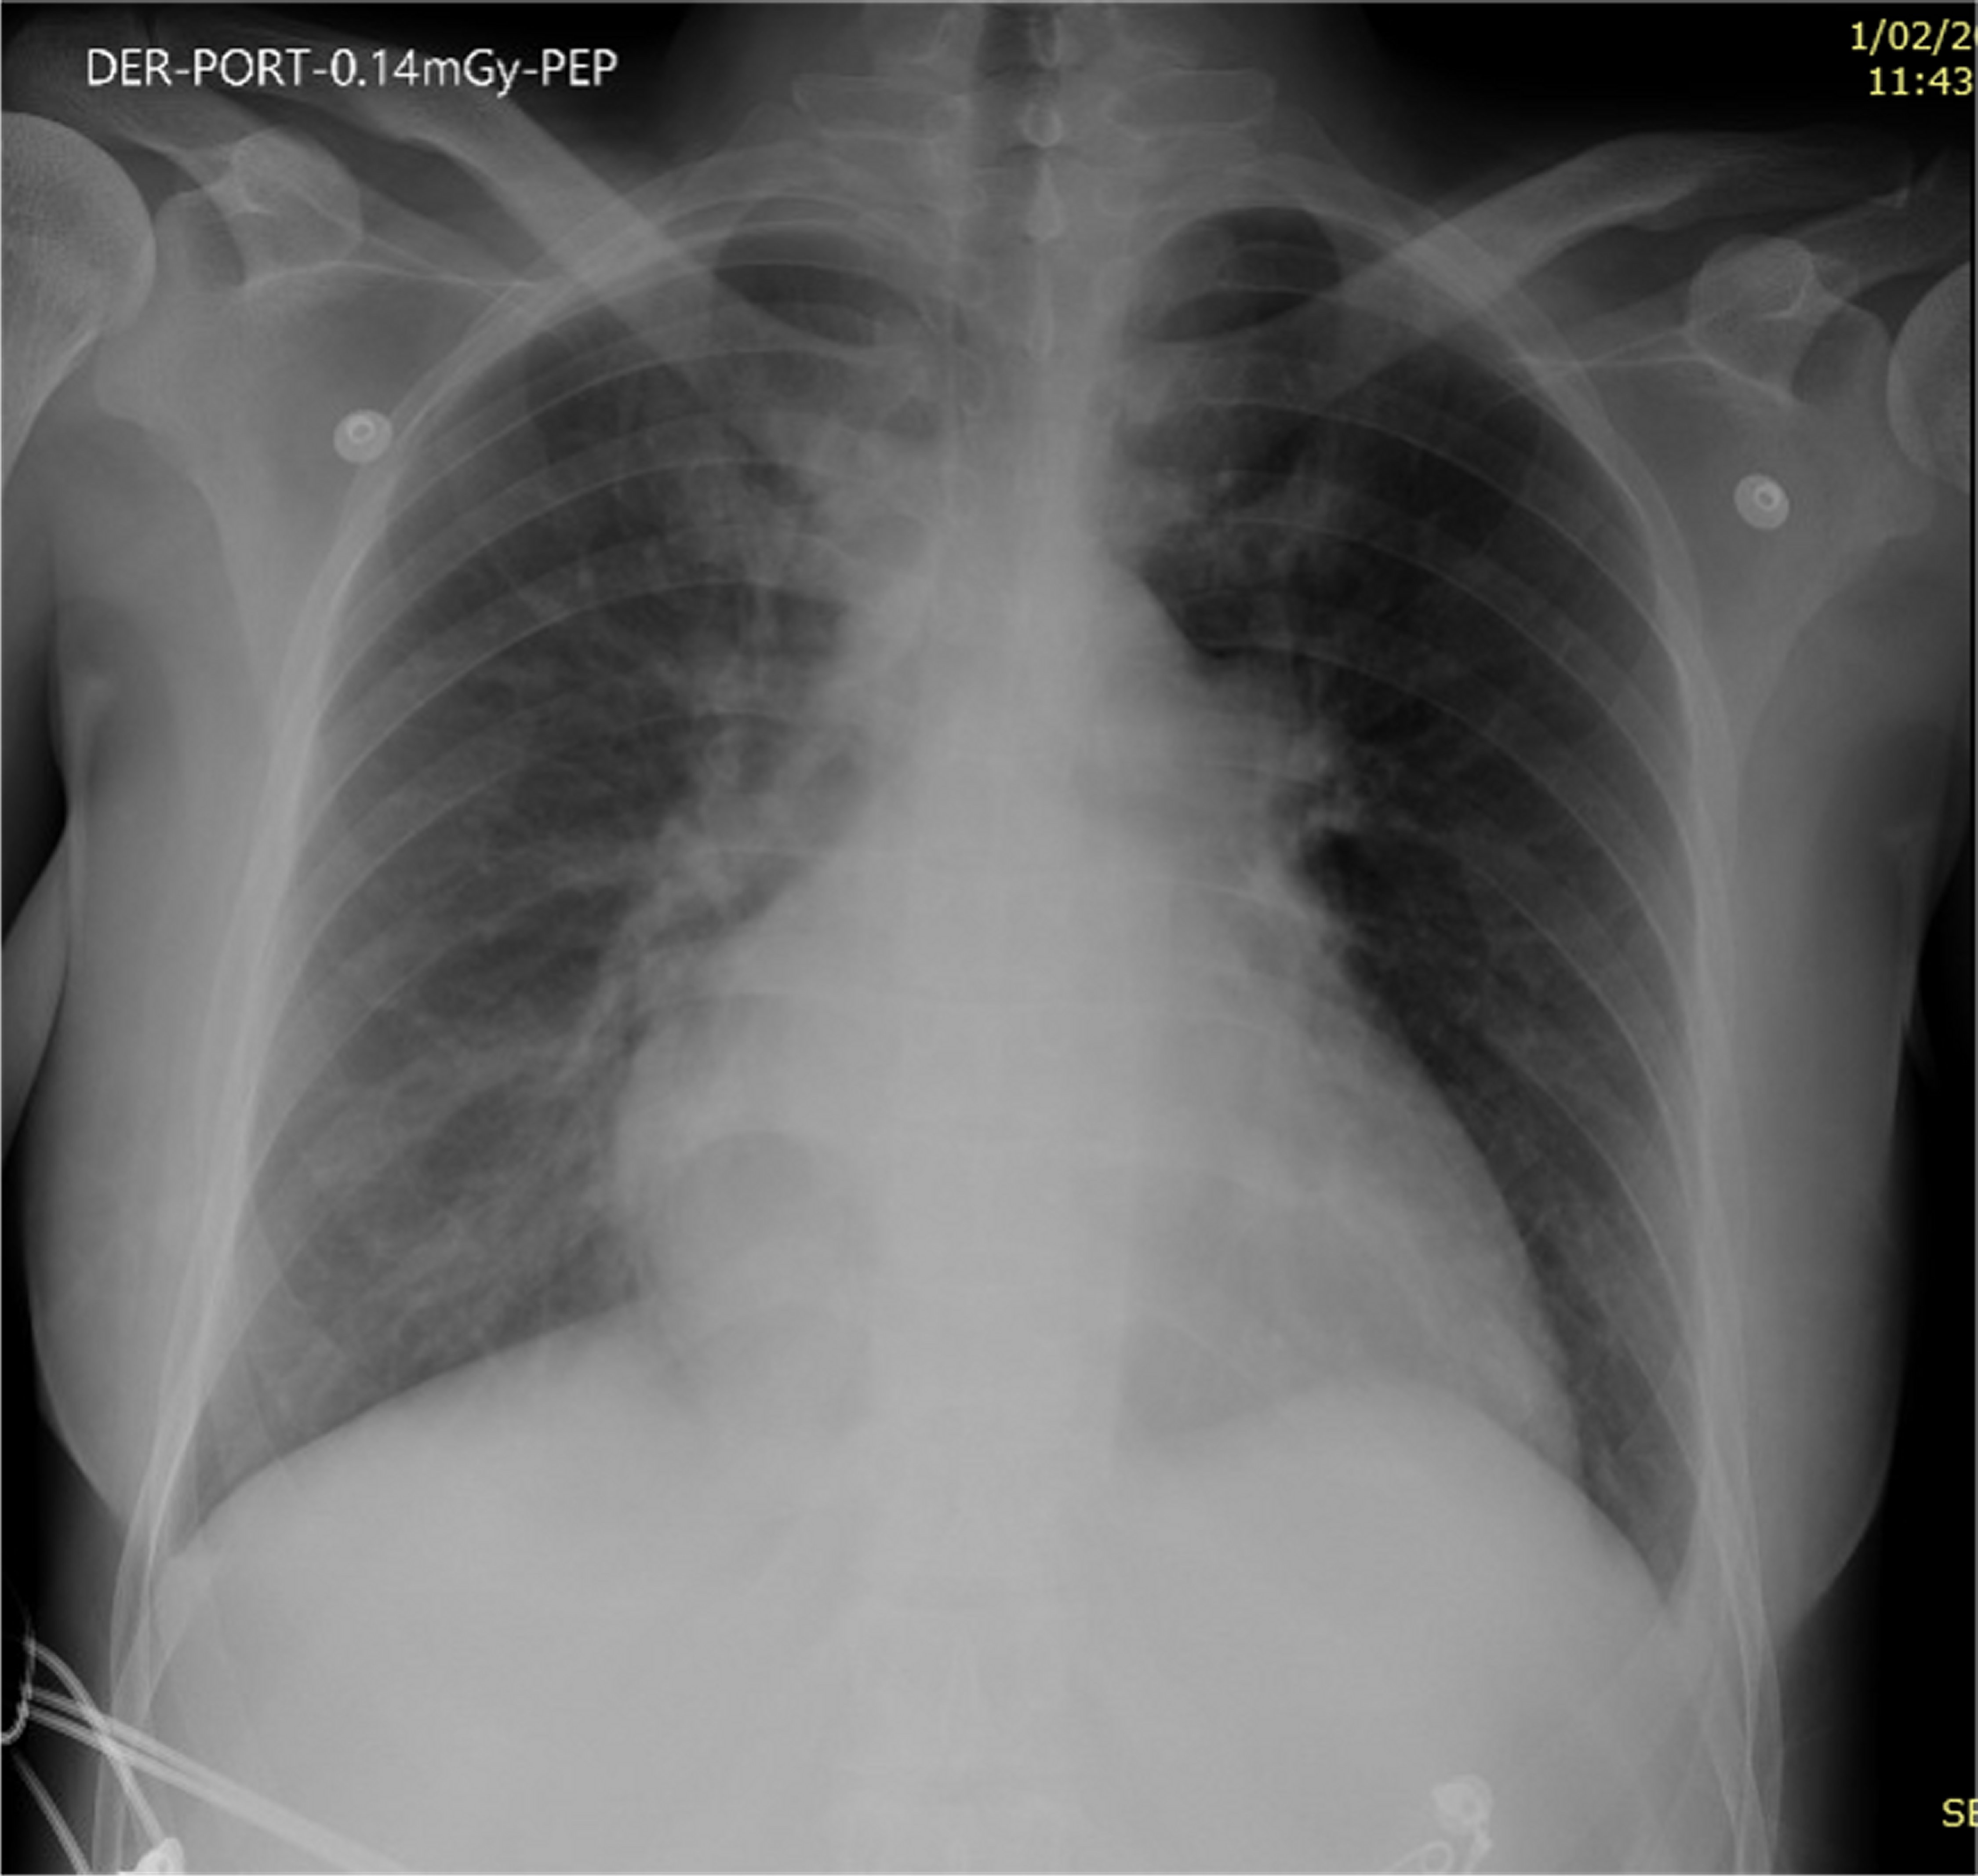

A chest X-ray was performed showing enlargement of the cardiac silhouette and bilateral interstitial infiltrates consistent with stage 2 acute pulmonary edema (Figure 1).